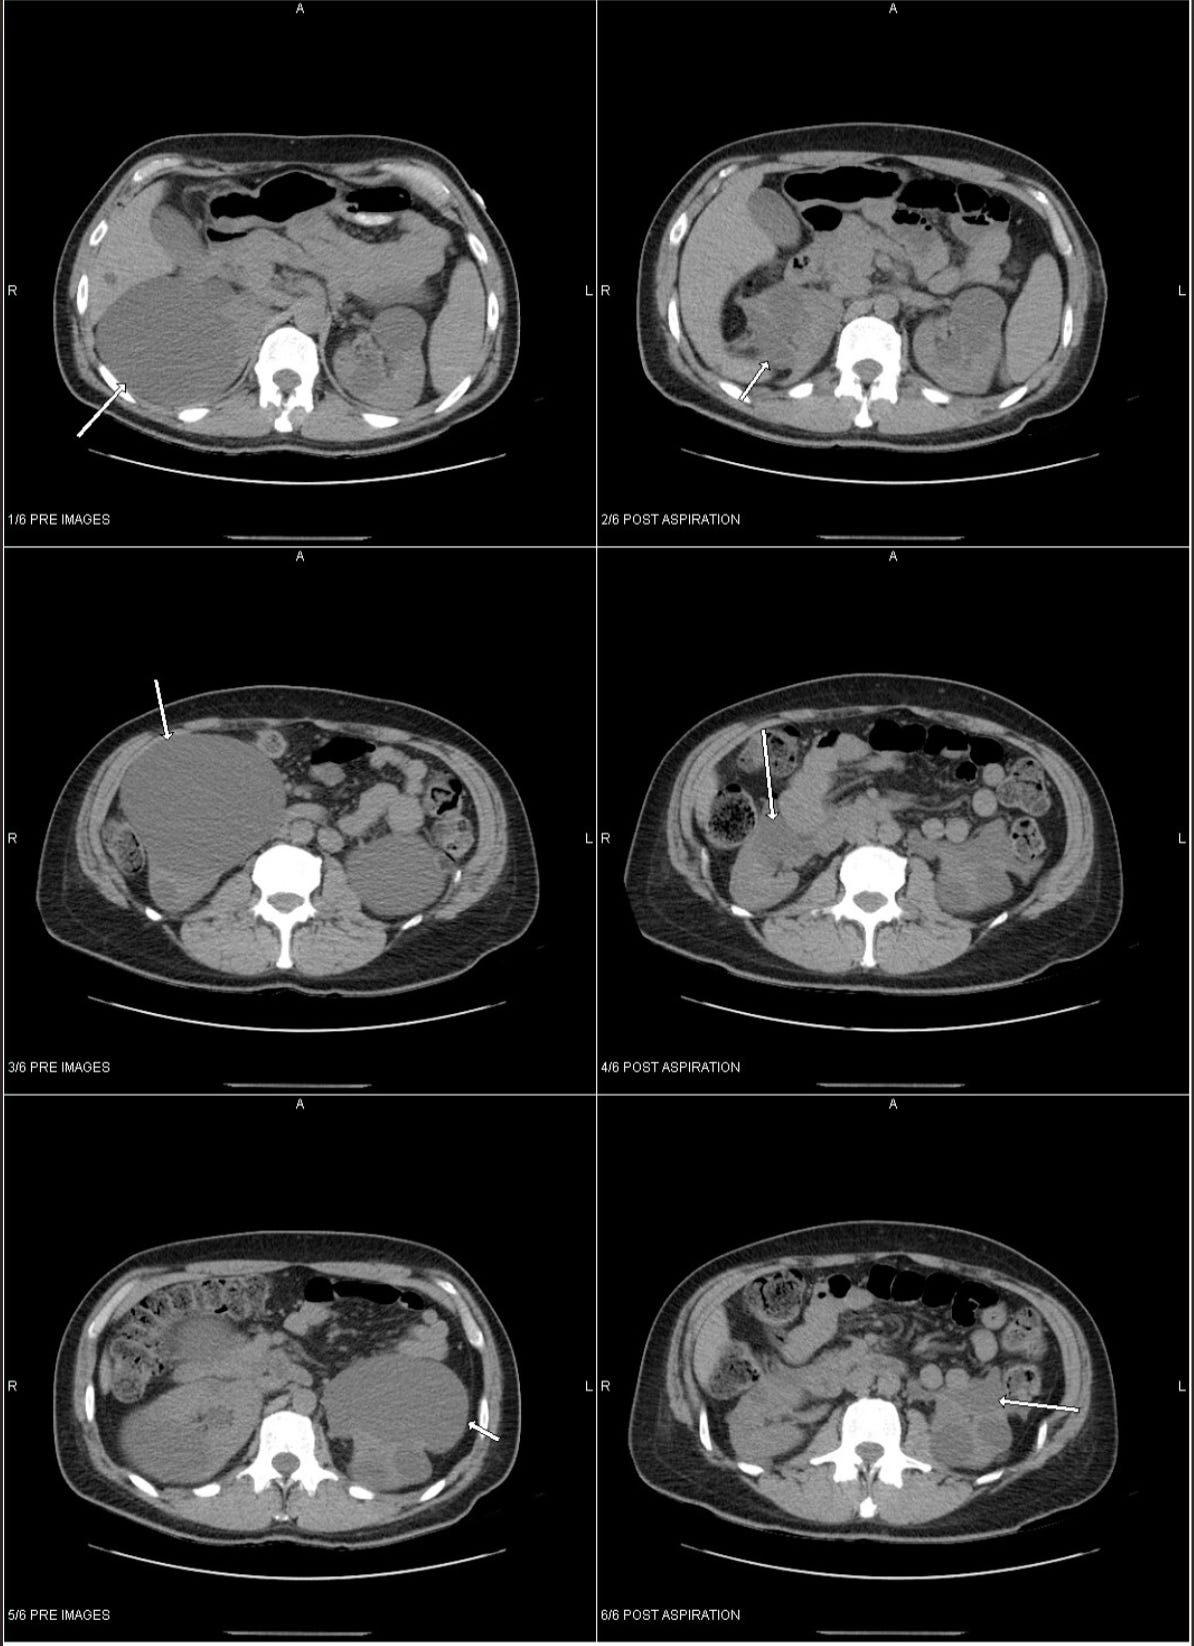

This is what I faced in the fall of 2016 - a 40oz worth of fluid around my right kidney and a cyst the same size as the one I have now was on my left side.

The left images are before, right images are after, and since this is straight from the radiologist, it’s swapped left to right, which makes my head hurt trying to mentally flip it around to match how I feel as I write this. They aspirate first, then wait a week, then the actual surgery to remove the cysts happens. This is post aspiration, it shows the size. The one on the right was 1300ccs - that’s a 40oz worth of fluid.